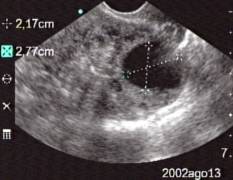

Data inserimento: 08 /05/2006Data esame: 13/08/2002 Strumento: Sonosite Età paziente: F 28 anni Diagnosi ecografica di gravidanza al sesto giorno di ritardo mestruale. Viene documentata la camera ovulare in utero, la presenza del corpo luteo all'ovaio destro. Elaborazione digitale: Andrea Dini